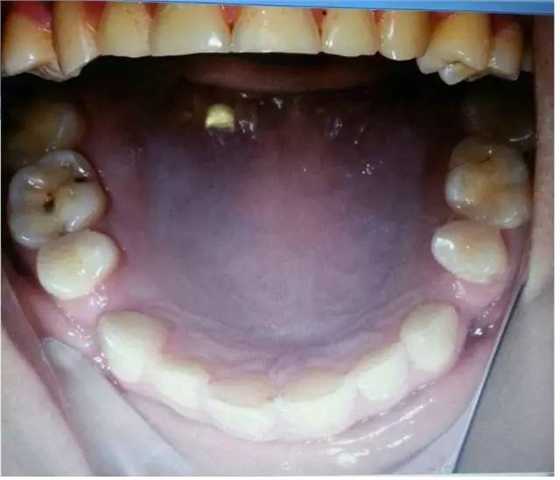

磨耗是超過生理范圍的牙體磨損,是一種病理性磨損,臨床上磨損可并發(fā)各種病癥或?yàn)橹虏∫蛩兀缫鹧辣举|(zhì)過敏、食物嵌塞、牙髓炎、顳頜關(guān)節(jié)病,以及口內(nèi)軟組織創(chuàng)傷性潰瘍,并可成為致癌的因素。

過大的(牙合)力通常是造成磨耗的原因,還有醫(yī)生指出,如患嬰兒式吞咽方式,舌頭在吞咽時(shí)會(huì)對(duì)牙齒產(chǎn)生推力,導(dǎo)致應(yīng)力集中的頸部出現(xiàn)微折裂也是原因之一。以上幾點(diǎn)都是造成牙體缺損的機(jī)械因素哦!其實(shí)這個(gè)病例給了我們很多信息,需要我們細(xì)致的檢查和問診,來吧,跟著權(quán)老師探究隱藏在表象之下的真相:牙齒出現(xiàn)缺損除了機(jī)械因素,還有什么因素?

是的,牙齒缺損還可能是化學(xué)因素造成的。權(quán)老師追問患者是否有胃病,追問飲食習(xí)慣,果真發(fā)現(xiàn)諸多玄妙之處。“患者喜歡吃酸東西,每頓飯必吃醋,吃完馬上就刷牙。”沒想到吧,這些看似不起眼的飲食習(xí)慣也能探究出與牙齒磨耗的因果關(guān)系,難怪群里郭耀銘老師忍不住感嘆權(quán)老師分享的病例酸味十足哩!這種酸酸的味道是要讓大家學(xué)會(huì)分辨機(jī)械因素和化學(xué)因素導(dǎo)致的牙體缺損。